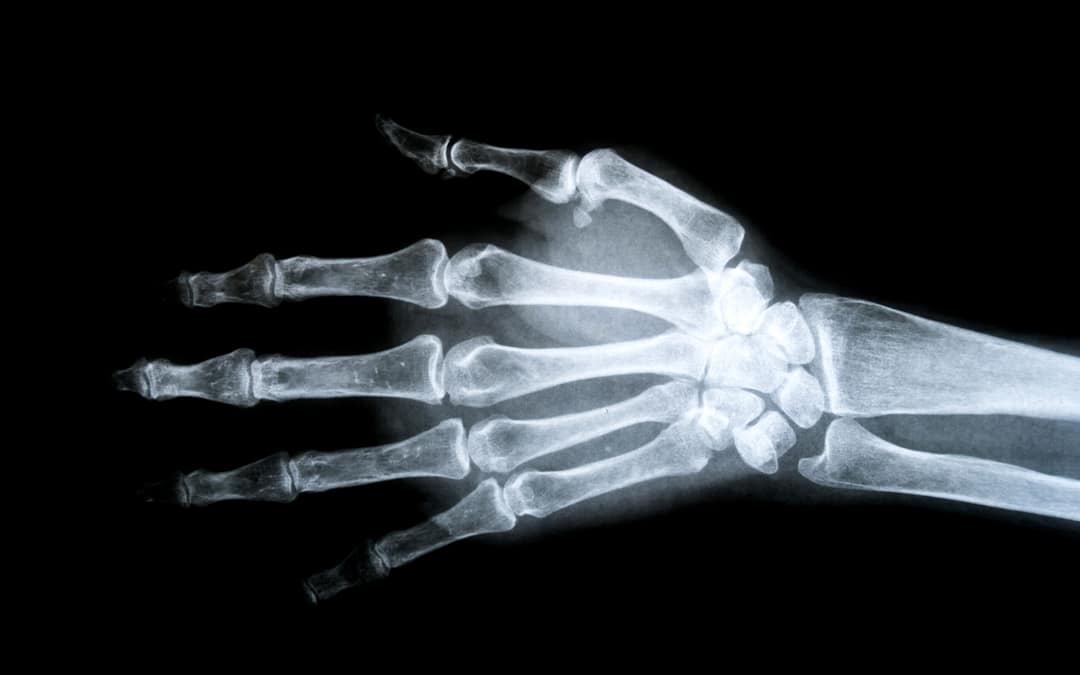

Fractures of the distal radius are common following sports injuries or falls. They often occur in people taking part in high energy activities, or in people with lower energy falls who have thin bones as a result of osteoarthritis. The vast majority of distal radius fractures can be managed without surgery, just using a plaster cast or a splint. If your fracture is completely undisplaced and your pain is under control in a splint, then a splint maybe all you need to get over this injury. This can be taken off to allow washing of your hand and to do some gentle exercises to try and reduce the long-term risk of stiffness.

If the fracture has moved apart a little bit in a backwards direction, then it’s often possible for our hand surgery team to gently relocate it for you and hold it there using a plaster cast. We would then talk to you about what the risks of the fracture displacing again might be, and this is usually dependent on how far bent back the bone was at the time of the injury, how weak or strong your bone quality might be, whether the ulna bone is also broken, whether the fracture goes into the joint or has stayed outside of the wrist joint.

If you choose to manage your fracture in a plaster cast, then this will usually be kept in position for between four and six weeks to try and reduce the risk of the bone slipping back again in the future. With mild slips backward, the functional results are often still very good, and although the wrist might always look a slightly different shape, often people return to excellent function without pain, even if the X-ray looks different to how it did before the break.